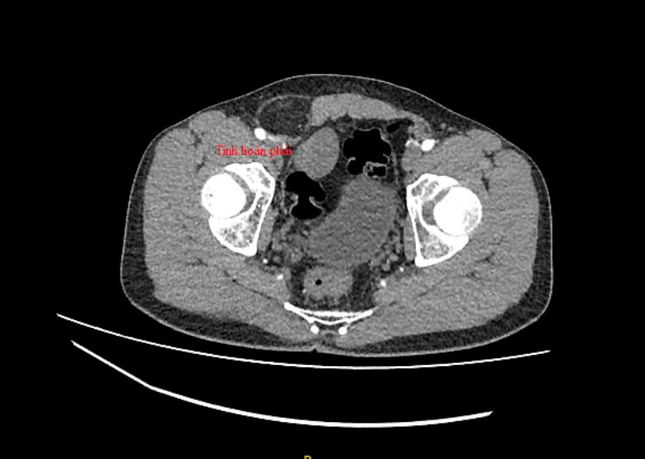

Qua kiểm tra hình ảnh, bác sĩ phát hiện khối thoát vị bẹn , đồng thời tìm thấy tinh hoàn bên phải trong ổ bụng nằm cạnh bàng quang của bệnh nhân. Sau hội chẩn, các bác sĩ đã quyết định thực hiện phẫu thuật cho người bệnh.

Trong quá trình phẫu thuật, ê kíp bác sĩ đã đưa các tạng thoát vị vào trong ổ bụng. Các bác sĩ đã thám sát và xác định tinh hoàn bên phải của bệnh nhân có kích thước tương đương tinh hoàn còn lại. Tinh hoàn bên phải nhanh chóng được giải phóng và đưa từ ổ bụng về vị trí sinh học ở vùng bìu cho bệnh nhân. Sau phẫu thuật, sức khỏe người bệnh nhanh chóng bình phục.